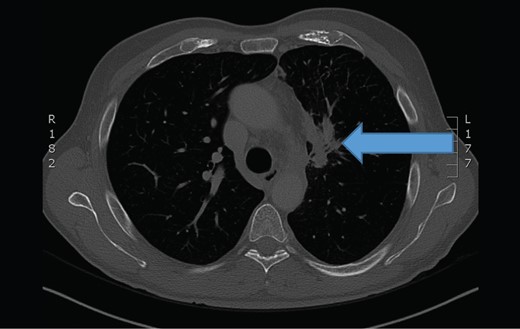

The chest computerized tomography scan showed a infiltrating tumor mass at the upper left lung (arrow).

Because of unknown origin of small intestinal metastases, the patient was referred to extensive diagnostics. Chest CT showed a large primary lung tumor in the left upper pulmonary lobe with pathological mediastinal lymph nodes. The patient was presented to multidisciplinary team and was later referred to oncology for further treatment.

In our case, small bowel obstruction was the initial clinical symptom for this patient. Primary lung cancer was suspected by a pathologist according to the immunohistochemical staining of metastatic lesion, that was taken from small bowel mesenterium during surgery. The diagnosis was later confirmed with chest CT, showing a large tumor mass in the left upper pulmonary lobe. The second abdominal CT confirmed diffuse small bowel metastases, that were found during emergeny surgery and metastases to both adrenal glands (stage IV).